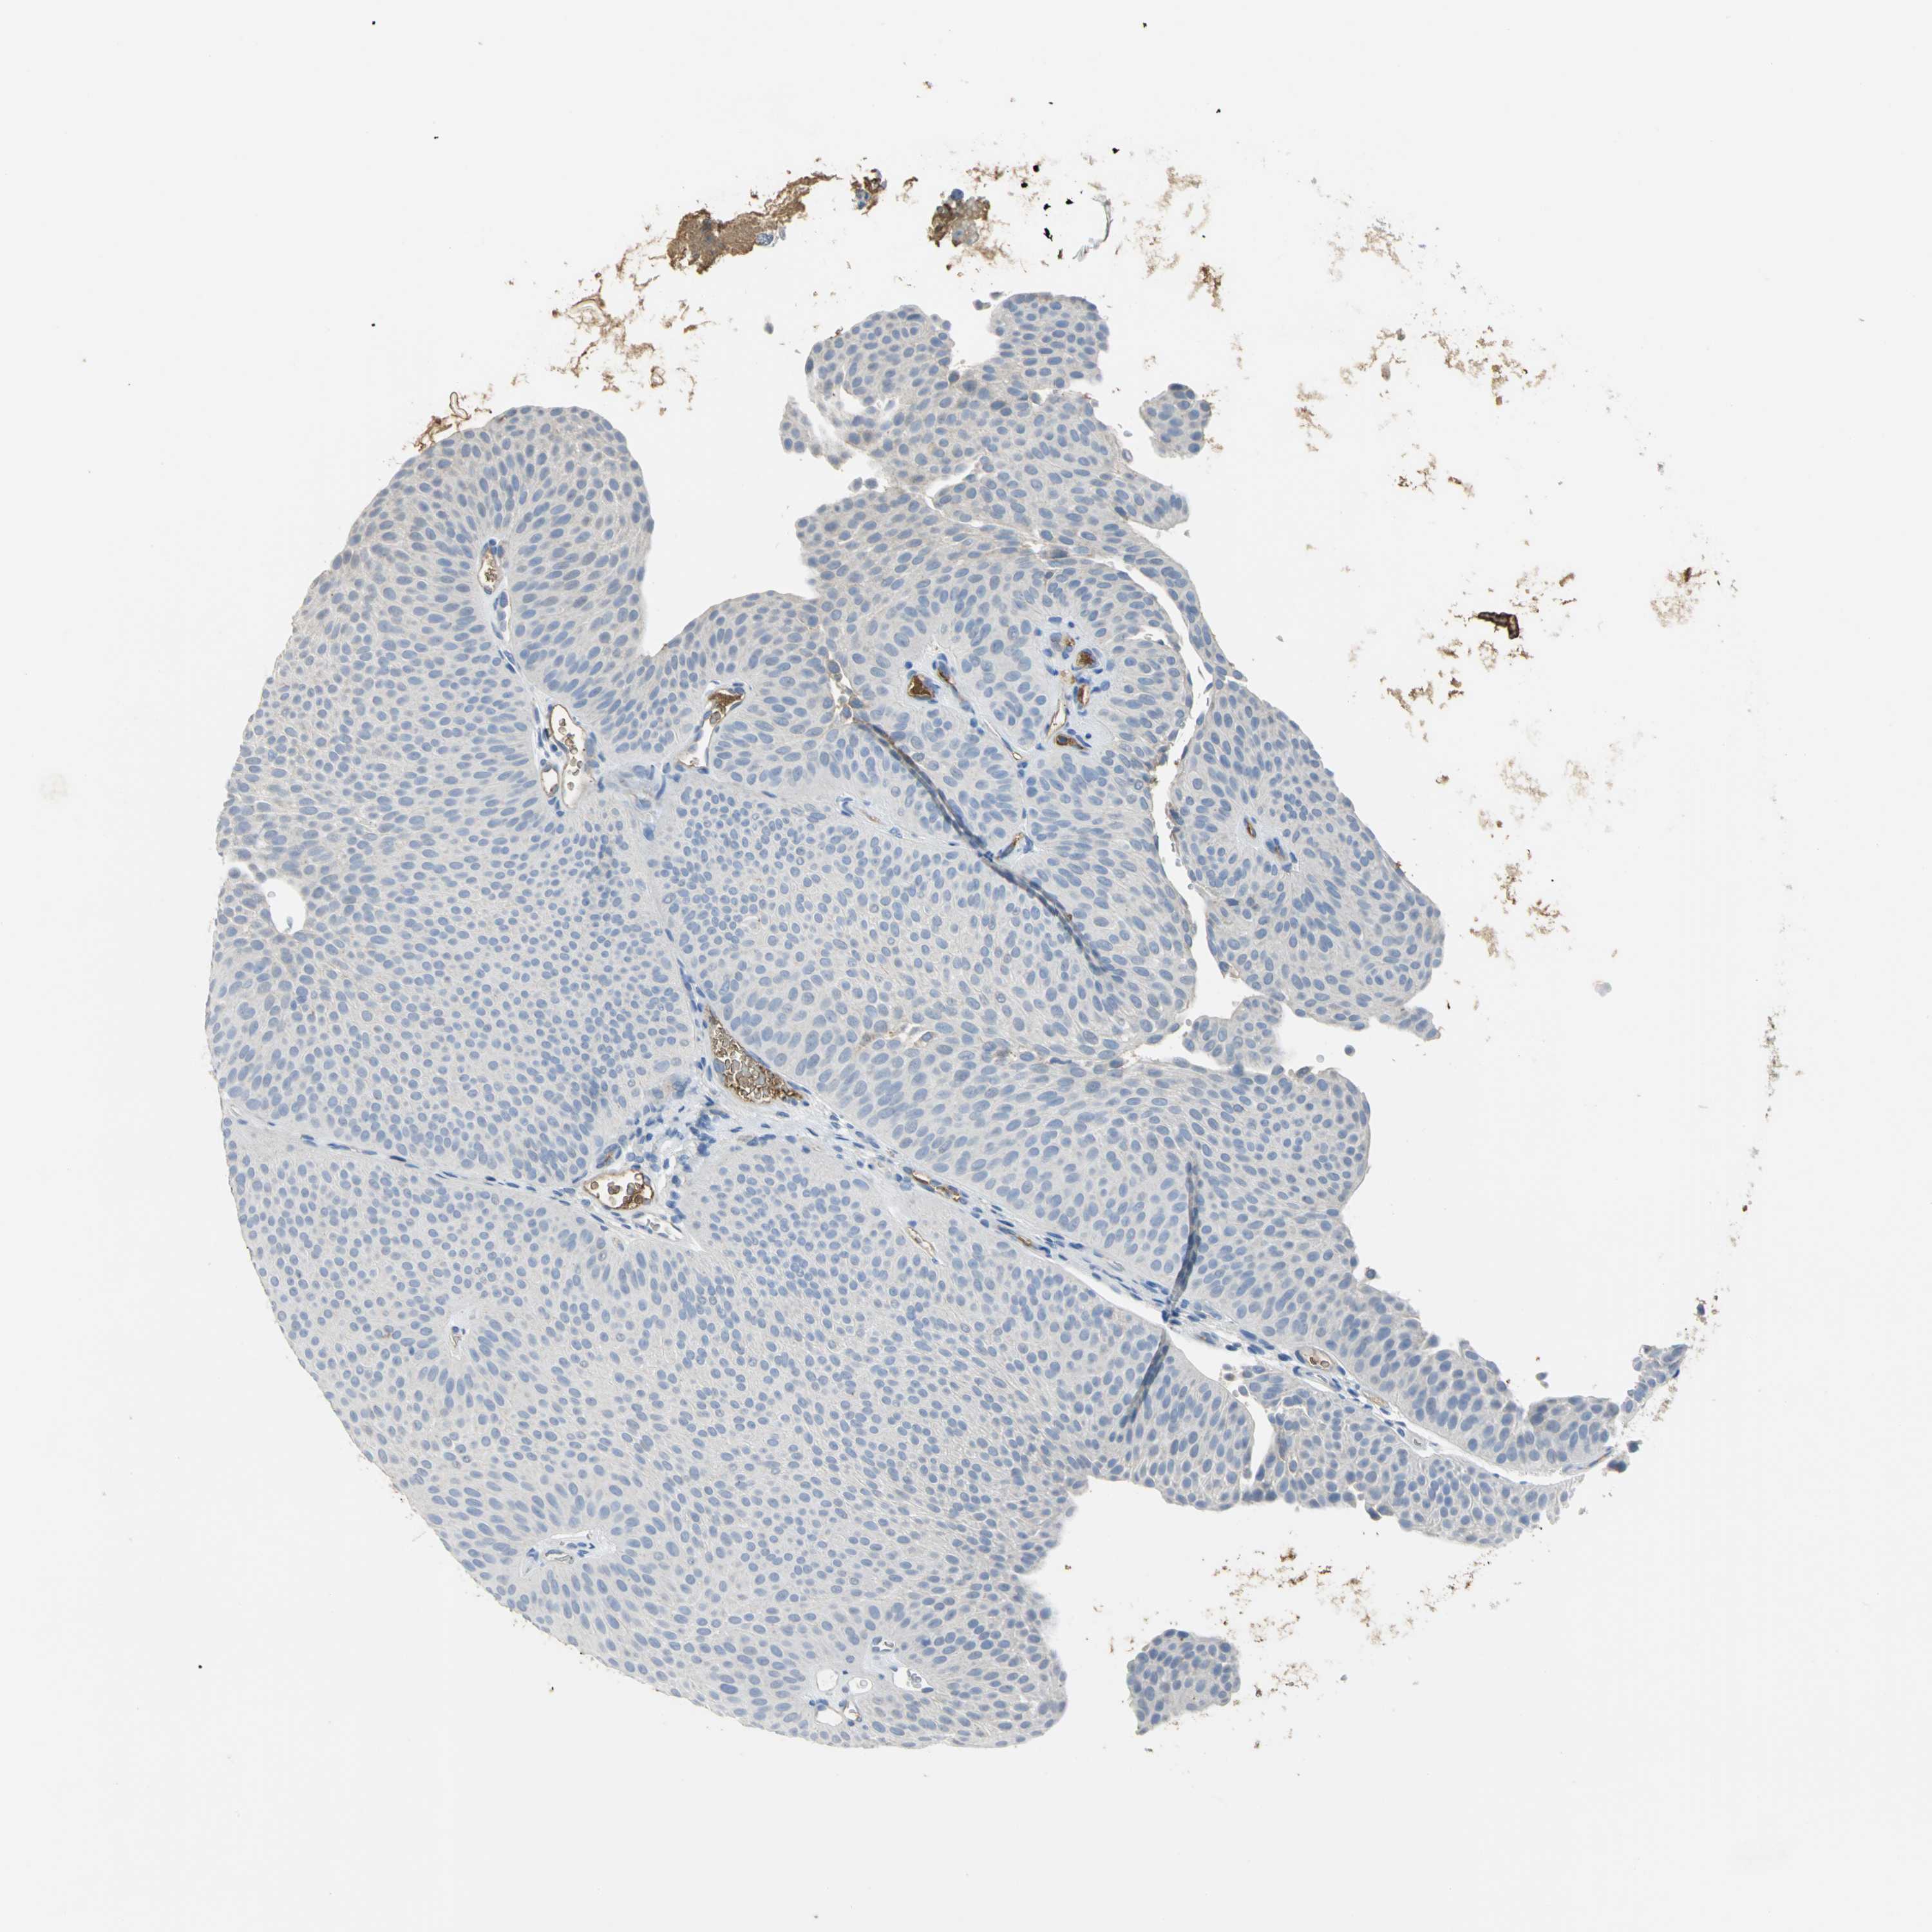

UROTHELIAL CANCER - Protein expressioni

A mouse-over function shows sample information and annotation data. Click on an image to view it in a full screen mode. Samples can be filtered based on level of antibody staining by selecting one or several of the following categories: high, medium, low and not detected. The assay and annotation is described here.

Note that samples used for immunohistochemistry by the Human Protein Atlas do not correspond to samples in the TCGA dataset.

Antibody stainingi

Antibody staining in the annotated cell types in the current human tissue is reported as not detected, low, medium, or high, based on conventional immunohistochemistry profiling in selected tissues. This score is based on the combination of the staining intensity and fraction of stained cells.

Each image is clickable and will lead to virtual microscopy that enables deeper exploration of all samples and also displays staining intensity scores, fraction scores and subcellular localization as well as patient and tissue information for each sample.

Antibody HPA005495

Antibody HPA064686

Staining

High

Medium

Low

Not detected

Intensity

Strong

Moderate

Weak

Negative

Quantity

>75%

75%-25%

<25%

None

Location

Nuclear

Cytoplasmic/membranous

Cytoplasmic/membranous,nuclear

Urothelial carcinoma, High grade

Urothelial carcinoma, Low grade

Urothelial carcinoma, NOS